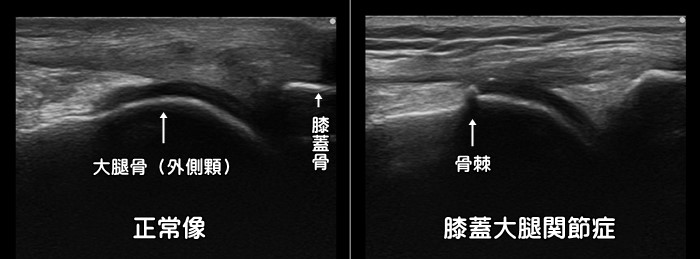

膝蓋大腿関節症

膝のお皿の骨(膝蓋骨)がその下にある大腿骨とすれる・ぶつかる事で痛みが発症します。ランニング・ロードバイク・階段昇降動作などで症状が発症します。最初は膝を屈伸する際の膝の皿の裏側の違和感や引っ掛かり感から始まり、進行すると痛みが出現します。